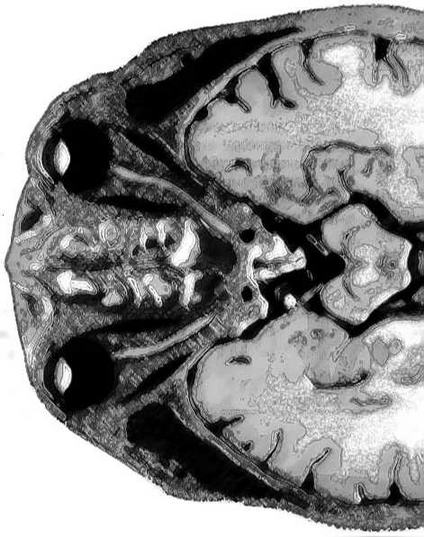

Сегодня отследить его динамику помогают точнейшие сканерные и измерительные технологии. Не только ЭЭГ, но и целый набор томографий и спектроскопии отражает электрическими или магнитными полями своеобразную «карту ГОЭЛРО» со вспышками мозговой активности. Нужна поистине фантастическая чуткость приборов: любое математическое вычисление или чтение текста включает множество процессов, длящихся миллисекунды. Это как передача эстафетной палочки по нейронным лабиринтам неокортекса вплоть до узла закрепления понятия и готовности к действию.

Участники маленького «мозгового штурма» совершили экскурс в механизмы памяти, приоткрытые последними отечественными и зарубежными экспериментами. Профессор Алексей Латанов из МГУ показал уникальные кинокадры: радиотелеметрия позволила ему исследовать, что творится в гиппокампе голубя, потерявшего и нашедшего путь к голубятне. А вот движения глаз обезьяны при восприятии жизненно важной информации. Загадочно, почему мышь, освоившая путь в лабиринте, с трудом его находит после периода кормления жирной пищей. Что там, синапсные джунгли увядают от обжорства? Может, это еще одно предупреждение гурманам? А вот почти «живая» микроскопная картинка: химические нейромедиаторы вызывают в культуре мозга мыши тот же рост соединительных отростков между нейронами — аксонов с синапсами, который мы предполагаем и от обучения. Где здесь «курица», где «яйцо»?